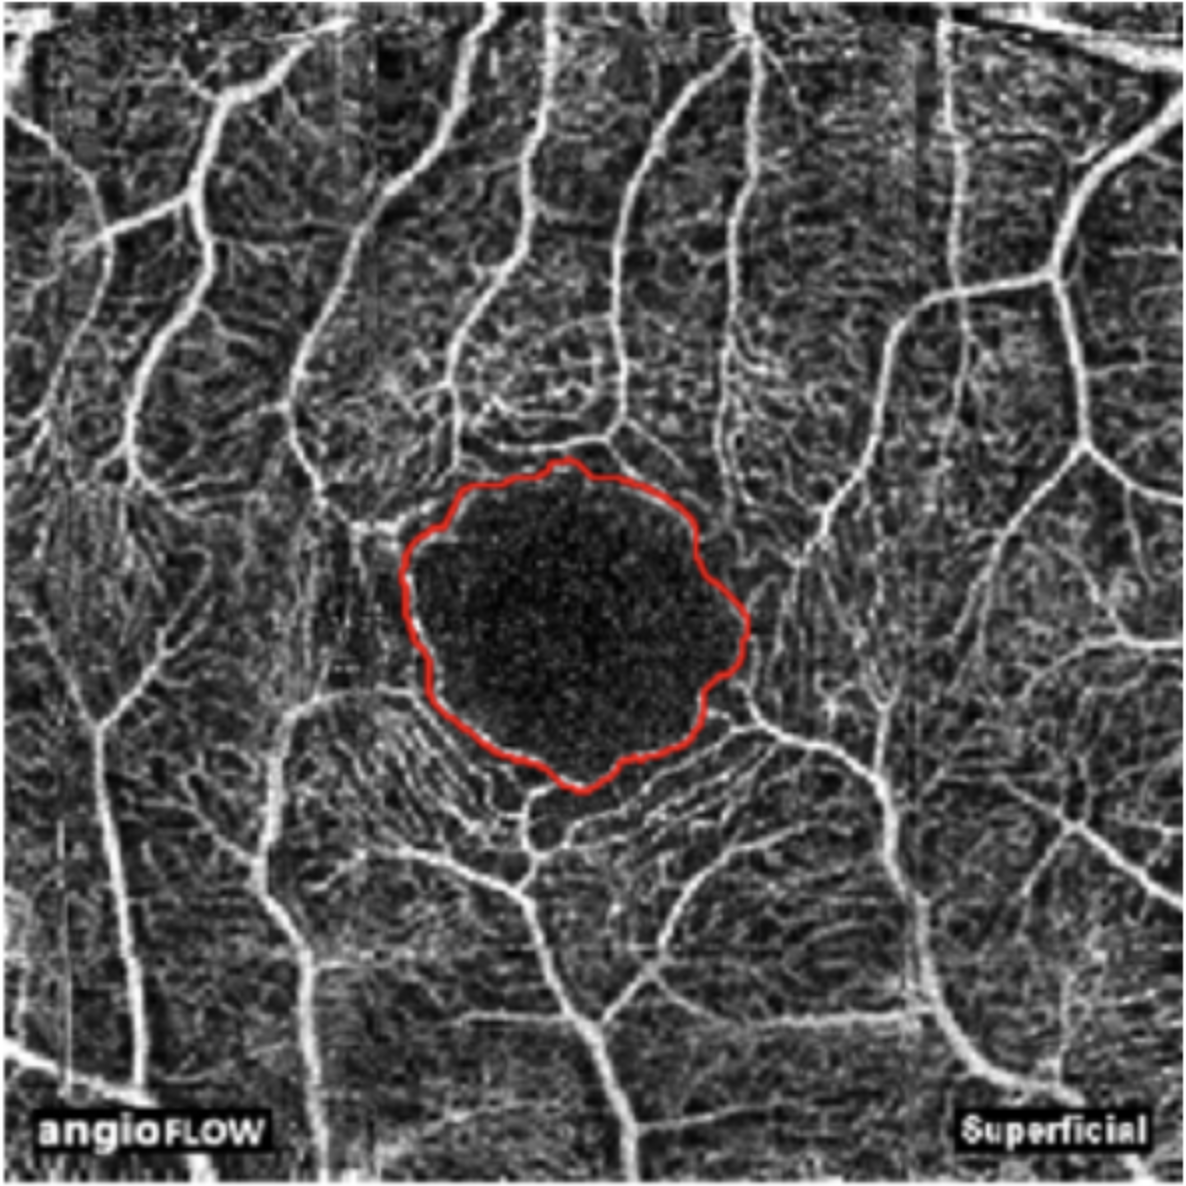

work EyeNote Clinical Information Extraction for Ophthalmology Reasoning Engine An AI-Assisted Differential Diagnosis System for Ophthalmology MuDaRI Multilabel Dataset of Retinal Images for Detection of Multiple Ocular Diseases FAZSEG Automatic Foveal Avascular Zone Segmentation Using Hessian-Based Filter and U-Net Deep Learning Network BCI Mental Workload Monitoring mental workload during sensorimotor rhythm BCI training using functional near-infrared spectroscopy over the prefrontal cortex Fractals EEG Motor Imagery Investigating fractal dimension as a non-linear correlate of event-related desynchronization in motor imagery EEG fun WEEG SSVEP game A portable, wireless 8-channel EEG system with SSVEP-based BCI game and real-time signal processing software Infrared Heart Rate Monitor A photoplethysmography pulse sensor built from scratch with IR LED, photodiode, and analog signal conditioning, for a Biophotonics module project